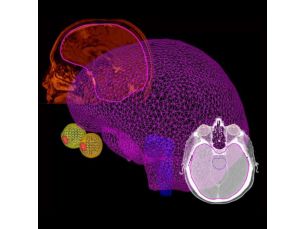

Planificación de tratamiento Pinnacle3

Las herramientas de planificación de tratamiento rápidas, precisas e interactivas han convertido a Pinnacle³ en un líder en planificación de tratamiento de radiación. Con una reputación de rendimiento, fiabilidad y un entorno de planificación flexible e intuitivo que simplifica el flujo de trabajo, Pinnacle³ se ha convertido en el producto de elección de muchos centros oncológicos líderes a nivel mundial.